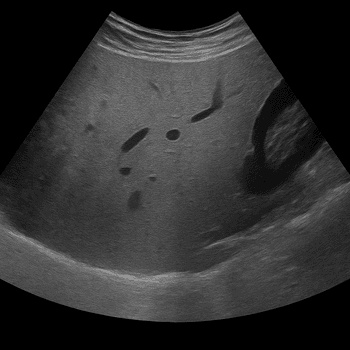

The examination provides high-resolution images of the liver's structure, blood flow and bile ducts and is used both in cases of suspected disease and for follow-up of previous findings. MRI is the most sensitive method for distinguishing benign from malignant changes and can often provide more information than ultrasound or computed tomography.

- Investigation of cysts, nodules or suspected tumors in the liver.

- Check for known changes, such as hemangioma or focal nodular hyperplasia (FNH).